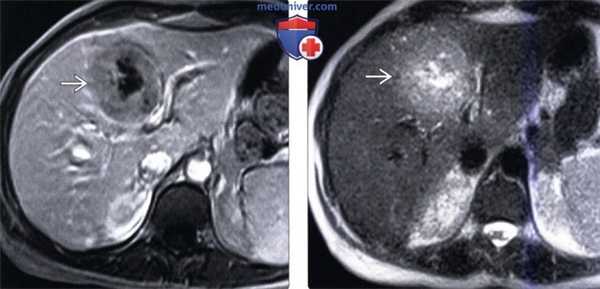

(Слева) На аксиальной КТ без контрастного усиления у юноши 17 лет с пальпируемым образованием в эпигастрии визуализируется большая опухоль с включениями кальция. Настолько крупные кальцинаты практически никогда не обнаруживаются в узлах ОНГ.

(Справа) На КТ в артериальной фазе контрастного усиления у этого же пациента определяется неравномерное контрастное усиление образования; видна также крупная артерия , осуществляющая его кровоснабжение. (Слева) На КТ в артериальной фазе контрастного усиления у этого же пациента определяется неравномерно повышенное накопление контраста в образовании; визуализируется также опухолевый тромб, вызывающий расширение воротной вены. Обратите внимание на метастатическое поражение регионарных лимфоузлов, которые, так же, как и опухоль, выглядят гиперваскулярными. У пациента также обнаружены метастазы в легких.

(Справа) На КТ в венозной фазе контрастного усиления у этого же пациента определяется, что опухоль по-прежнему неоднородна, имеет место также некоторое вымывание контраста в опухолевом тромбе внутри воротной вены. Визуализируются вторично измененные лимфоузлы; видны также кальцинаты в опухоли. (Слева) На Т2 ВИ МР томограмме у девушки 20 лет с жалобами на раннее насыщение и снижение веса визуализируется большое, неоднородное образование, замещающее левую долю печени. Обратите внимание на гипоинтенсивный центральный рубец.

(Справа) На аксиальной Т1 ВИ МР томограмме с контрастным усилением у этой же пациентки образование остается неоднородным. Была выполнена резекция опухоли и лимфатических узлов, поскольку альтернативные методы лечения при обнаружении опухоли у молодой пациентки отсутствуют, а циторедуктивная операция доказано способствует повышению выживаемости.